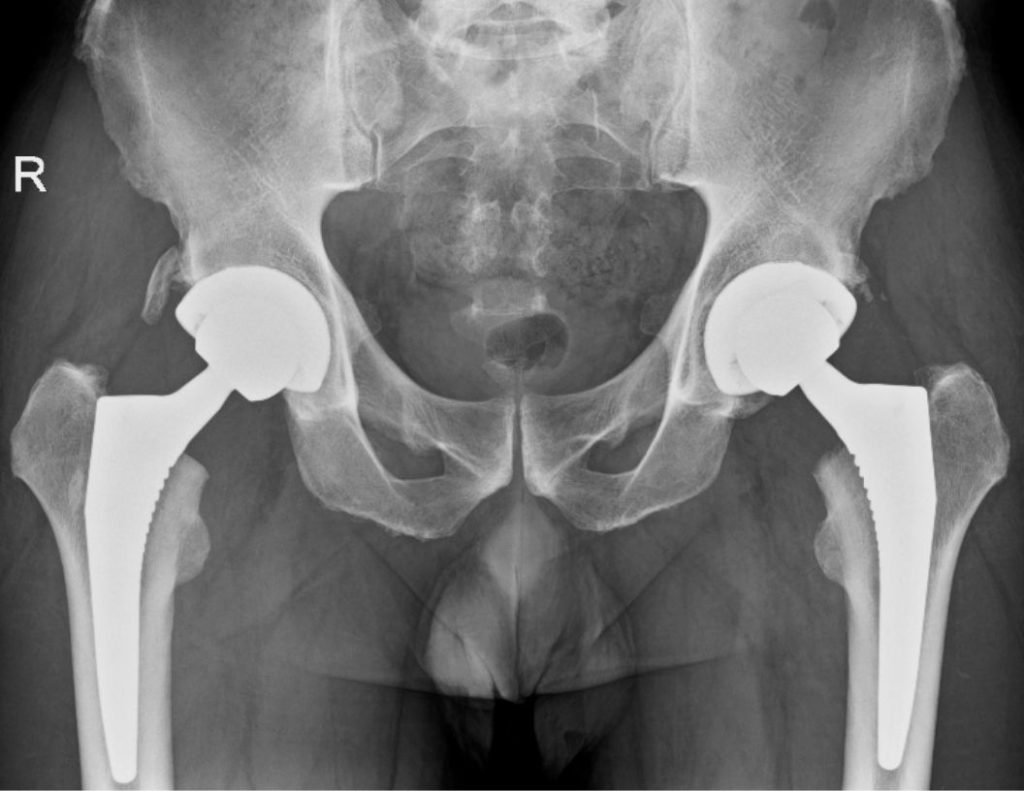

Coxartosi bilaterale

dopo